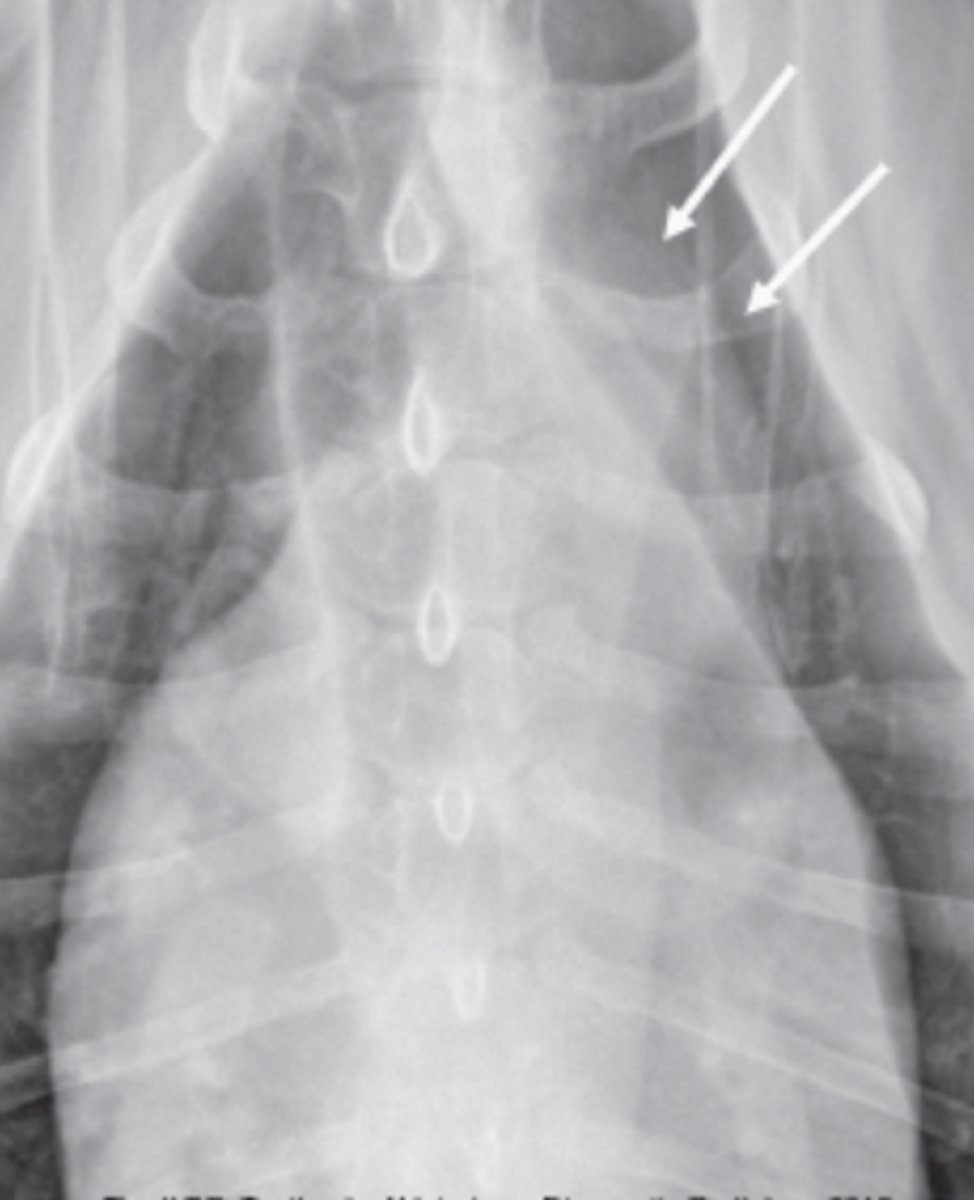

dilatación-torsión gástrica

patología: